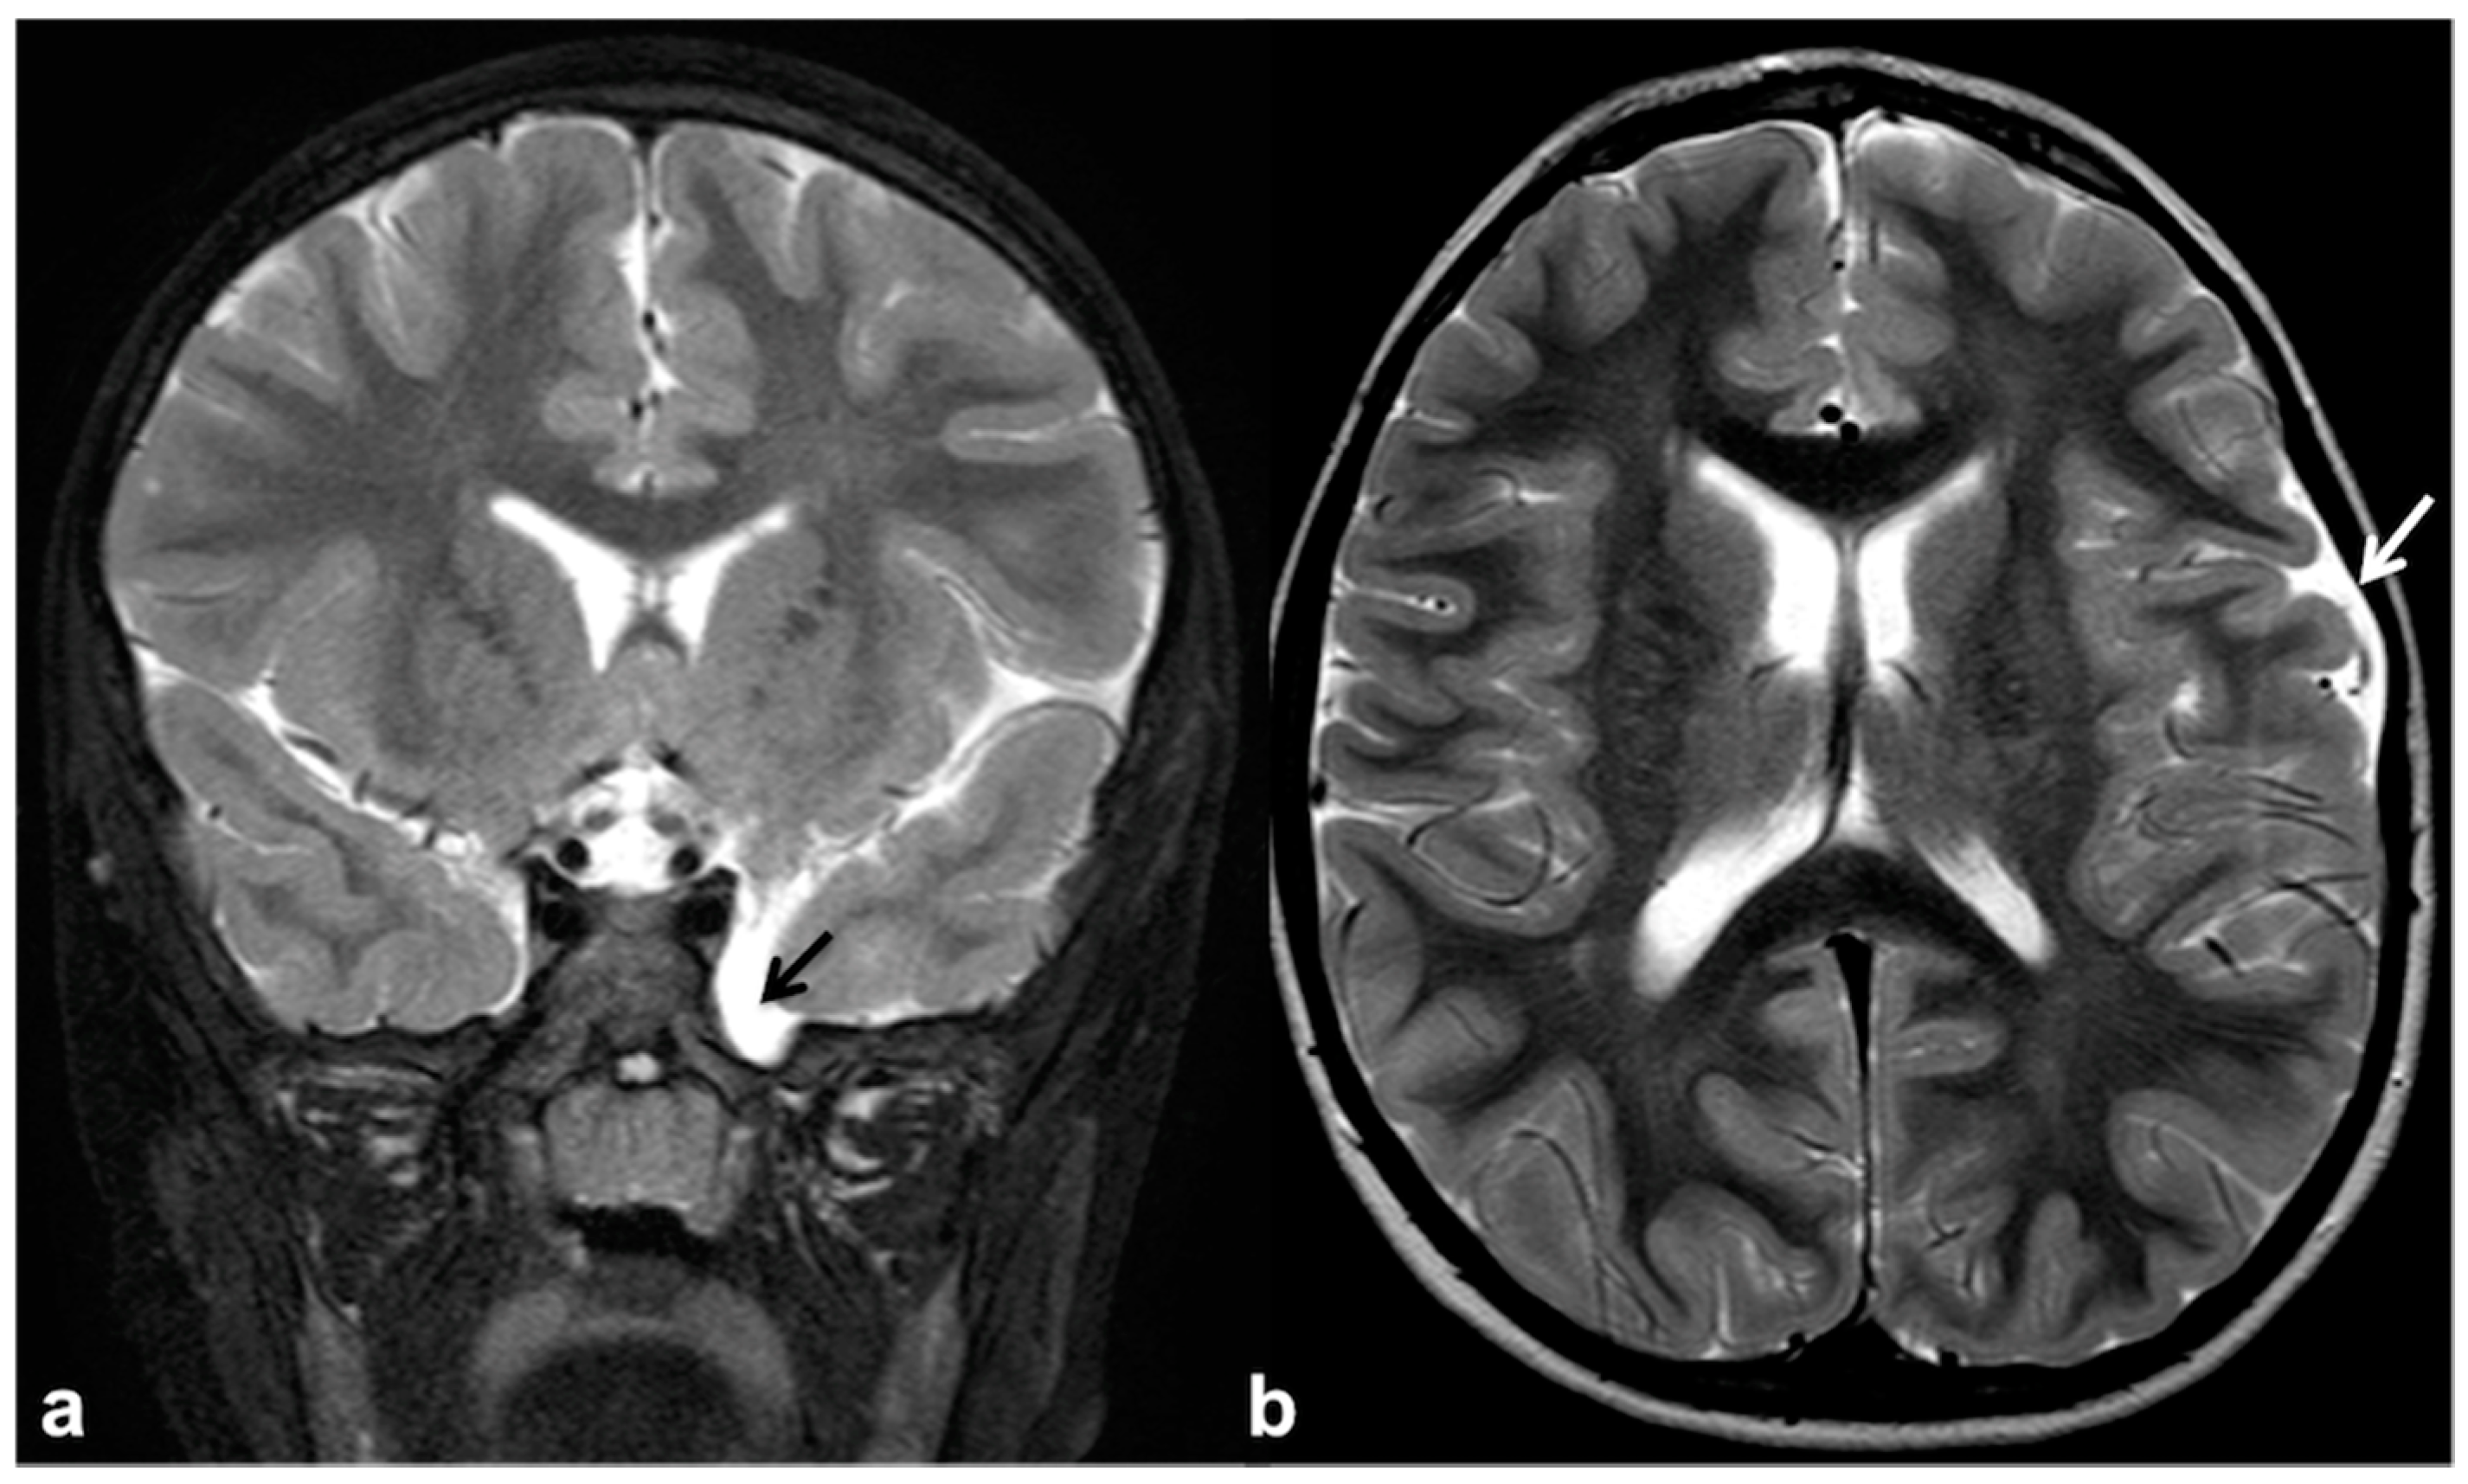

2.3. Epileptogenic Lesions in NF1

2.4. Altered Cerebrospinal Fluid Dynamics: Obstructive Hydrocephalus Other Than Tumor-Related